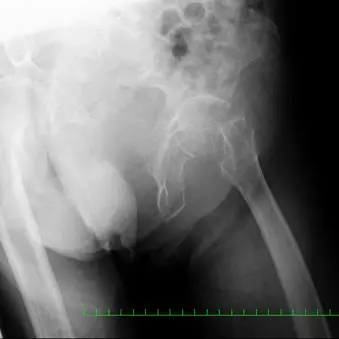

89歳女性。自宅にて歩行中に転倒受傷し、当院の救急外来へ搬送された。来院時の股関節単純エックス線像(図1)において左大腿骨頚部骨折(Garden3型、Müller AO分類31-B2)を認め、手術施行目的にて当科入院となった。受傷前のADLは杖を使用して独歩可能であった。既往歴は高血圧、高脂血症、アルツハイマー型認知症。また入院時諸検査において特記すべき事項はなかった。

(図1)単純レントゲン像